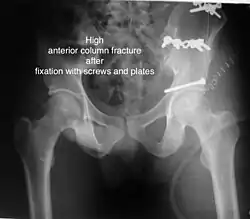

High anterior column fracture after fixation with screws and plates

| Anterior column | This fracture is uncommon, typically occurring when the injuring force is applied from the side, against the greater trochanter of the femur bone, as in a fall on the side or being hit on the side. Depending on the location, the fractures are described as very low, low, intermediate and high anterior column fracture. | Anterior column + posterior hemi transverse | In this variety of fractures, the posterior or ilio ischial column is broken as a transverse fracture, while the anterior or ilio pubic column is broken into multiple pieces. Part of the weight-bearing dome in this variety of fractures is still attached to that part of the iliac wing, which forms part of the iliac joint. This type of injury has to be differentiated from both column fractures, where the weight-bearing dome is a floating piece not attached directly to the bone-forming sacroiliac joint.

Typically, it is caused by a combination of forces acting on the hip through the femoral head. All three X-ray views plus a CT scan are a must for the diagnosis and management of this complex injury. In this injury, non-operative treatment rarely gives satisfactory results. Surgical management is ideal. The choice of approach rests with the surgeon but going from the front or anterior approach is necessary. The posterior injury may be tacked with the anterior approach by an experienced surgeon. If the patient is unfit to undergo major surgery due to any reason, longitudinal traction to achieve secondary congruence of the hip may help to restore hip function, though partially. |